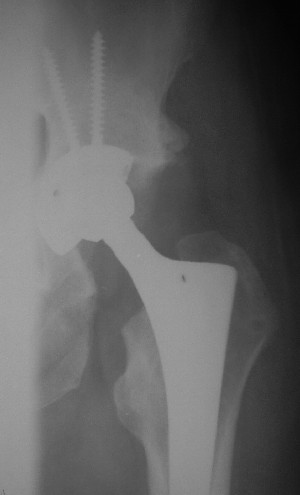

Больной 18 мая 2003 года в автоаварии получил перелом левой вертлужной впадины, вывих бедра. Госпитализирован в один из стационаров области.Вывих вправлен. В последствии бедро вывихивалось еще дважды. На консультацию был представлен снимок от 19.05.03г., больной переведен к нам 3.06.03г. Снимок при поступлении - перелом впадины, задне-верхний вывих бедра. 05.06.2003 г. выполнено открытое вправление вывиха левого бедра и остеосинтез стенки вертлужной впадины двумя винтами. Послеоперационный период без осложнений. Объем движений в левом тазобедренном суставе восстановился полностью. Выписан на амбулаторное лечение в удовлетворительном состоянии с рекомендациями 3 месяца ходить на костылях без нагрузки на оперированную конечность. На контрольных рентгенограммах левого тазобедренного сустава 13.10.2003 г. - признаки консолидации перелома; плотность, форма головки и состояние суставных поверхностей удовлетворительные. Разрешена дозированная осевая нагрузка, на конечность с использованием дополнительной опоры. 19.12.2003 г. больной обратился с жалобами на боли в левом тазобедренном суставе. На рентгенограммах левого тазобедренного сустава 19.12.2003 г., 20.02.04г. - асептичекий некроз головки бедра. 5.04.04г. - эндопротез. Сейчас ходит без трости, не хромает. Особенность эндопротезирования - при удалении винтов прослежена линия перелома заднего края впадины и предложено установить чашку несколько меньшего диаметра, чтобы она была покрыта несломанной частью.